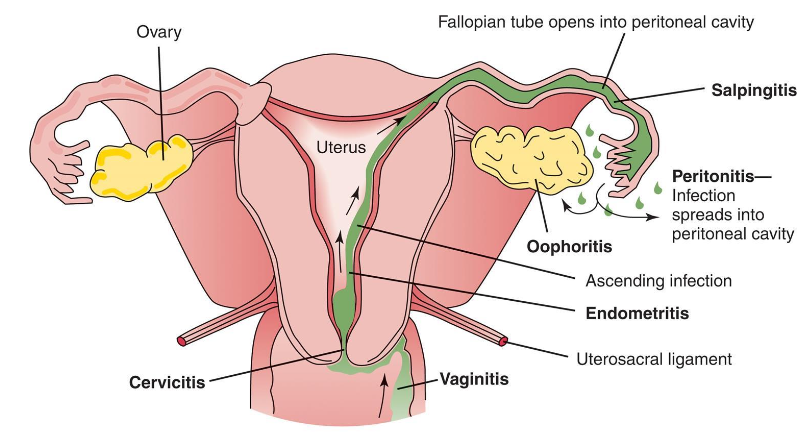

Endometrial thickening or fluid may indicate _______________ ?

………… is an infection within endometrium of the uterus.

It occurs most often in association with PID, in postpartum state, or following

instrumentation of uterus.

In patients with pelvic infection, uterus is conduit for infectious spread to tubes and

adnexa.

Postpartum patients may develop endometritis after prolonged labor, vaginitis,

premature rupture of the membranes, or retained products of conception.

Clinically, patient has intense pelvic pain.

Sonographically, the endometrium appears prominent, irregular, or both, with a

small amount of endometrial fluid.

Pus may be demonstrated in the cul-de-sac as echogenic particles or debris.

Enlarged ovaries with multiple cysts and indistinct margins may be seen secondary

to periovarian inflammation.

Dilation of the fallopian tube shows fluid-filled tubular shapes in a folded

configuration and well-defined echogenic walls.

A thickened tubal wall (5 mm or more) indicates acute disease. These should be

distinguished from a fluid-filled bowel by gentle compression on the pelvic wall to

look for peristalsis or movement in the bowel lumen.

Sonographic findings

Endometrium may appear thick, contain fluid, air or clot or appear

normal.

Endometrium considered normal up to 20 mm.

Measurement of >20 mm should raise suspicion of endometritis,

hemorrhage, or retained products of conception.

Risk for endometritis increases with premature rupture of

membranes, retained clot or POCs and prolonged labor.

As the infection worsens, periovarian adhesions may form and fuse the inflamed tube and

ovary, called the tubo-ovarian complex.

Further progression results in a tubo-ovarian abscess that appears as a complex

multiloculated mass with septations, irregular shaggy margins, and scattered internal echoes.

There can be posterior enhancement and a fluid-debris level. Gas bubbles are present in rare

cases; however, these also are observed in normal postpartum patients.

In the immediate postpartum period, the presence of retained tissue is difficult to distinguish

from inflammatory debris or blood clots.

The sonographic appearance can be similar to that of other adnexal masses, so clinical

correlation is important.

Sonography can also be useful in following the response to antibiotic therapy or in guided

transvaginal aspirations and drainage. If the aspirate is purulent, catheter drainage is used.

Endometritis